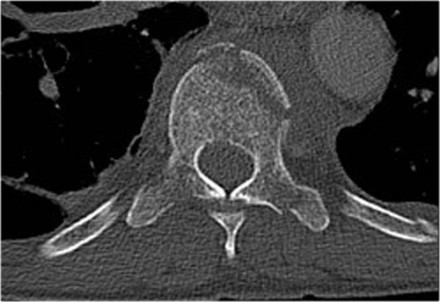

Widening of the interpedicular distance

Widening of the interpedicular distance, often a result of the sagittal fracture, is seen in 80% of burst fractures.

The lateral view shows the typical features of a burst fracture.

On the AP-view notice the subtle widening of the interpedicular distance compared to the levels above and below.

The axial CT and MRI in the same patient show the displaced fragment pressing on the thecal sac.

On the sagittal CT and MRI there are no signs of posterior ligamentous injury.

The anterior longitudinal ligament is disrupted.

The right facet joint looks a bit widened on the CT and there is some fluid in the joint on the MRI.

If there was a lot of fluid in the joint, we should call this indeterminate.

In this case we are not sure.